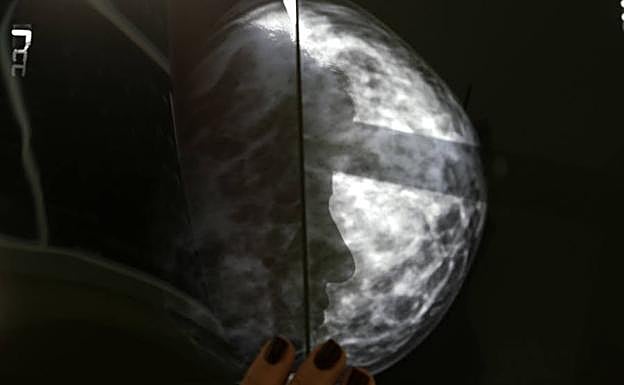

Mamografía. Reuters

La inteligencia artificial se adelanta al cáncer de mama

El MIT es capaz de predecir a partir de una mamografía si la paciente es propensa a desarrollar un cáncer de mama en el futuro

Para ello, el equipo de investigación han revisado un total de 90.000 mamografías de detección de alta resolución de aproximadamente 40.000 mujeres para entrenar, validar y probar el modelo de aprendizaje profundo. «Hay mucha más información en una mamografía que solo las cuatro categorías de densidad mamaria», señala Adam Yala, autor principal del estudio.

La densidad mamaria es un factor de riesgo independiente para el cáncer de mama que se ha agregado a algunos modelos para mejorar la evaluación de riesgos. El entrenamiento ha permitido a esta inteligencia artificial reconocer los sutiles patrones del tejido mamario que son precursores de su malignización.